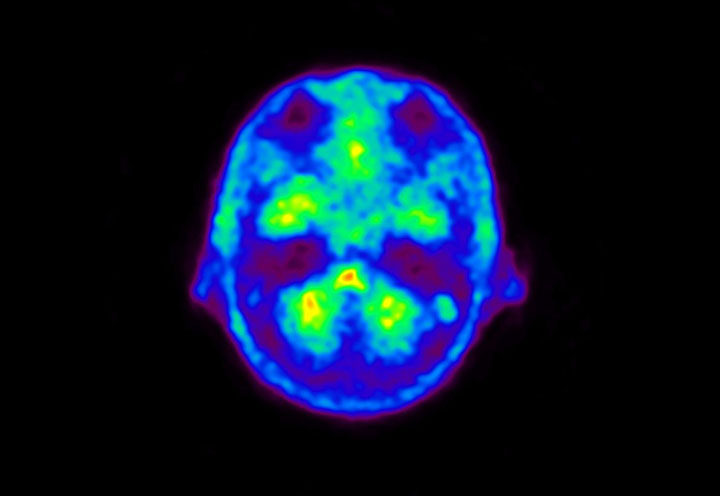

Head / Case5 : Amyloid

Coronal

Courtesy : Kindai University Hospital

- Imaging protocol

- Injected dose: 4.27 MBq/kg, 18F-Flutemetamol

- Uptake time: 99 minutes

- Scan time: 20 minutes